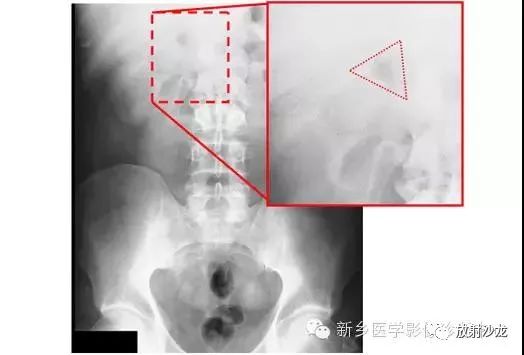

腹痛患者所做的腹部平片。有助于临床诊断的微妙征象是什么呢?

气腹患者摩里逊陷凹存在气体。平片中,靠近11肋的右上象限可见三角形(如在这种情况下)、半圆形,或月牙形的气体集聚。在仰卧位X光片中,右上象限的气体不能解释为肠道内气体,通常为腹腔内游离气体的最早迹象。

同一患者前-后坐位的胸片所示右膈下(箭头)游离气体,证实了气腹的诊断。